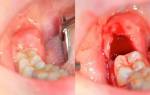

Пломбирование зуба и каналов является одной из наиболее востребованных стоматологических процедур. Обычно оно выполняется после лечения полости рта, зубов и десен, а также перед протезированием. Пломба помогает укрепить и частично восстановить поврежденную коронку, закрыть полость после удаления пульпы, создать опору для штифтов и искусственных зубов.

Современные стоматологические клиники все чаще используют фотополимерные и световые пломбы, которые цементируются слоями и моментально высыхают под воздействием УФ-лампы. Это позволяет прочно закрепить материал на зубной ткани. Однако, после такой процедуры возникает проблема питания. Обычно пломбирование зуба выполняется под местным наркозом, который продолжает действовать еще 2-3 часа после процедуры, вызывая онемение во рту. В связи с этим, не рекомендуется есть в первые часы после пломбирования. Это связано с риском получения ожогов или обморожений тканей из-за невозможности ощущать температуру пищи, искажением вкуса из-за нарушения работы рецепторов и повышенным риском травмирования мягких тканей при кусании и жевании. Некоторые стоматологи могут разрешать пациентам есть сразу после процедуры, но это является ошибкой, так как пациент должен быть осведомлен о возможных последствиях и нести ответственность за свои действия.